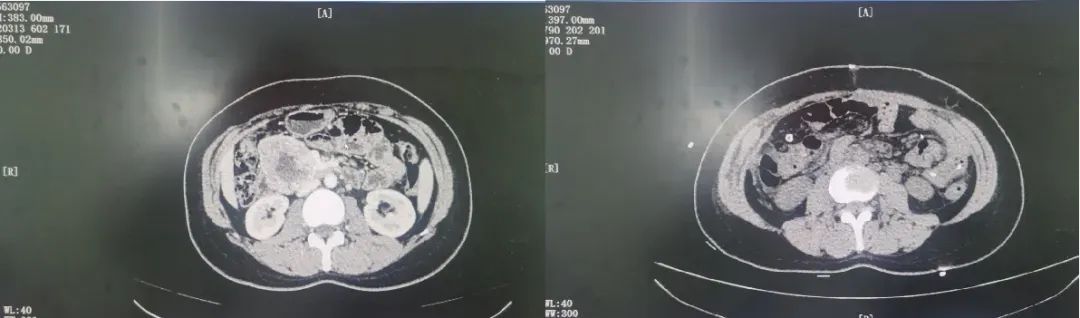

朱光辉主任医师凭借多年经验,术中准确探查,发现大小约8cm的腹膜后肿瘤侵犯十二指肠,按照既定手术方案,顺利完成腹膜后肿瘤切除联合胰十二指肠切除术。在麻醉科保驾护航下耗时5小时顺利完成手术,解除了这颗“定时炸弹”。

朱光辉主任医师介绍,腹膜后肿瘤位于人体腹盆腔的深处,由于位置隐匿、生长相对缓慢、症状不明显且没有特异性症状等,发现时往往已体积巨大,累及多个器官和脏器,治疗难度大。